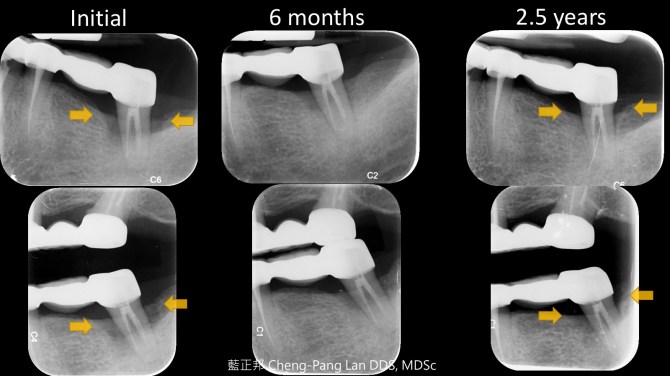

Non Surgical Therapy- Periodontal Regeneration – Case Rare 2 Posted on December 31, 2017 by drlan 最早部落格成立的初衷,是老師退休回美後,想看我的案例,於是,我把一些放在網路上。 完成後,老師卻不是要看這些,她只想看一些奇怪、特殊案例,但我怎麼回想,都找不到。 雖然這個老師應該不會有興趣,但對我來說,這個案例和另一個一樣是罕見、特殊案例。 65歲女性,喜啃甘蔗,全口磨耗,治療後已戒除。一開始,沒把握,僅僅只做Scaling & Root Planing與口腔衛教,未做咬合調整。兩年半後,很驚訝地持續穩定。圖片中可以看到疾病恢復過程。 2017年末,收到病患的一個跨年禮物。 新年快樂。 ps. 給年輕醫生:這種案例不是常態,請注意。 Share this: Share on Facebook (Opens in new window) Facebook More Email a link to a friend (Opens in new window) Email Share on X (Opens in new window) X Share on Pinterest (Opens in new window) Pinterest Share on Tumblr (Opens in new window) Tumblr Like Loading...